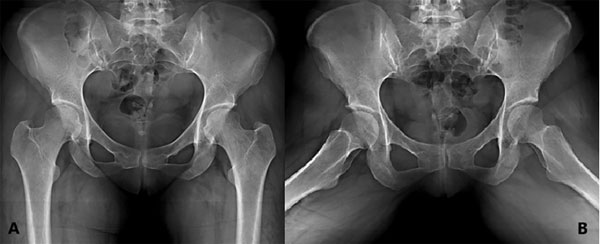

Figura 2: Paciente femenino de veintinueve años quien se sometió a artroscopía de cadera izquierda. A) Radiografía donde se evidencia lesión de Pincer y Cam. B) Radiografía de control donde se aprecia la correcta osteoplastia.